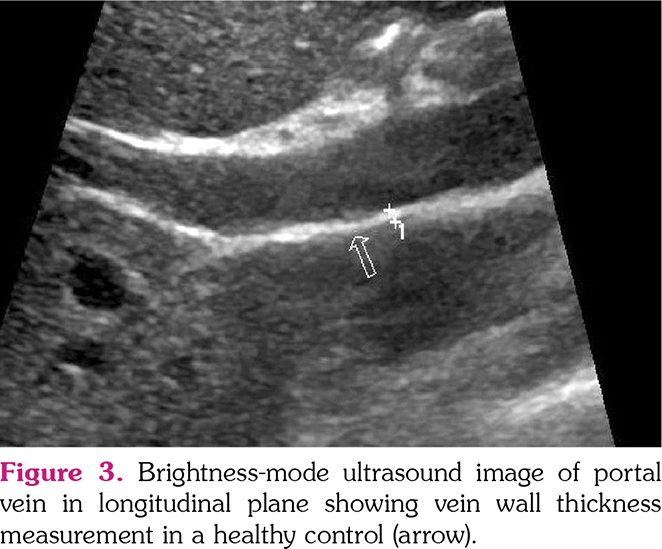

All US examinations were performed by an aboard-certified radiologist with seven years of experience in US imaging who was blinded to cases on the same day with clinical assessment. A second radiologist with an experience of three years in US imaging performed IMT and VWT measurements of the first 20 individuals on the same day with the first radiologist to evaluate the inter-observer agreement. All US examinations were performed after a fasting period of 6 h. Bilateral CIMT, jugular vein, and common femoral VWTs were measured using a 4-15-MHz ML6-15 linear transducer (Logiq E9, General Electric Company, Fairfield, CT, USA). mesenteric, The portal vein, inferior vena cava, superior renal, and splenic VWTs were measured using a 2-8-MHz 9L-D linear transducer (Logiq E9, General Electric Company, Fairfield, CT, USA). US examinations were performed with a high-resolution US system (LOGIQ E9; GE Healthcare, Wauwatosa, WI, USA). VWTs were evaluated during the Valsalva maneuver and IMT was measured during neutral breathing in the supine position. All veins were evaluated in both longitudinal and transverse planes. CIMT was automatically measured in a longitudinal axis using the Auto-IMT application (GE Healthcare, Wauwatosa, WI, USA). Three measurements were performed by the observers from each vessel and the average of these measurements for each vessel was noted (Figures 1-3).